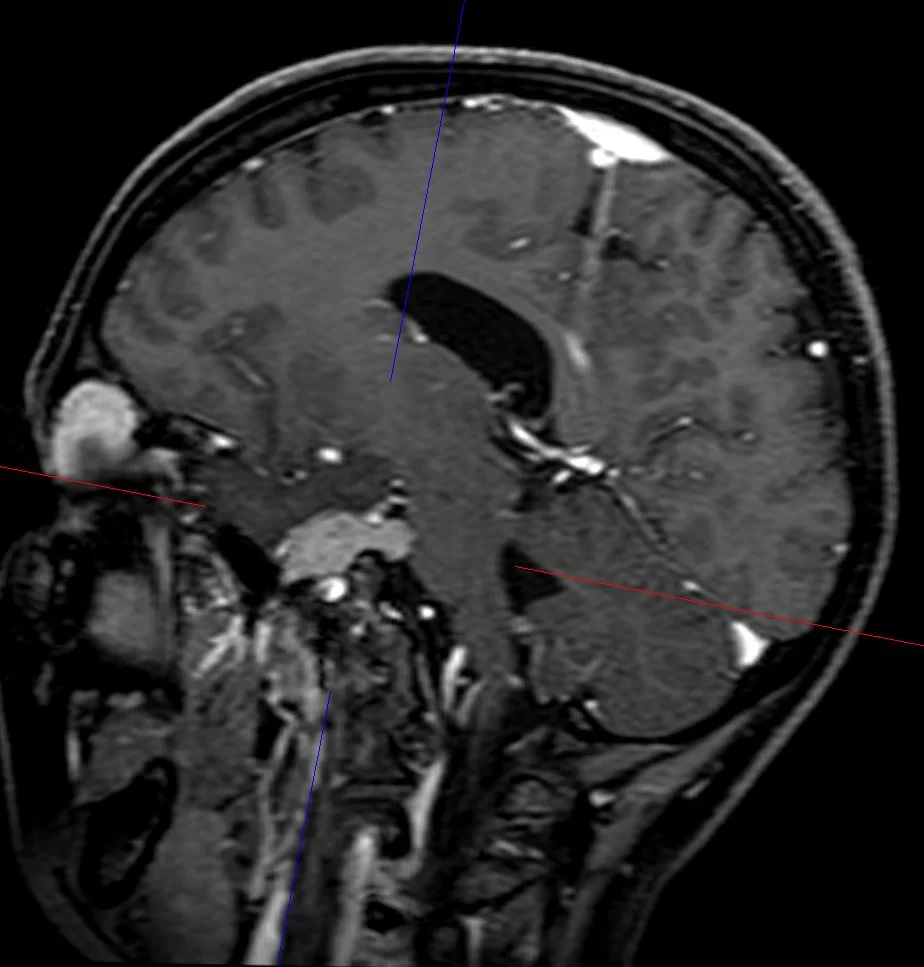

Η μαγνητική τομογραφία εγκεφάλου ανέδειξε χωροκατακτητική εξεργασία στην περιοχή του τριδύμου νεύρου αριστερά.

Η μετεγχειρητική μαγνητική τομογραφία εγκεφάλου δείχνει ένα εξαιρετικό αποτέλεσμα, με πλήρη αφαίρεση της βλάβης.